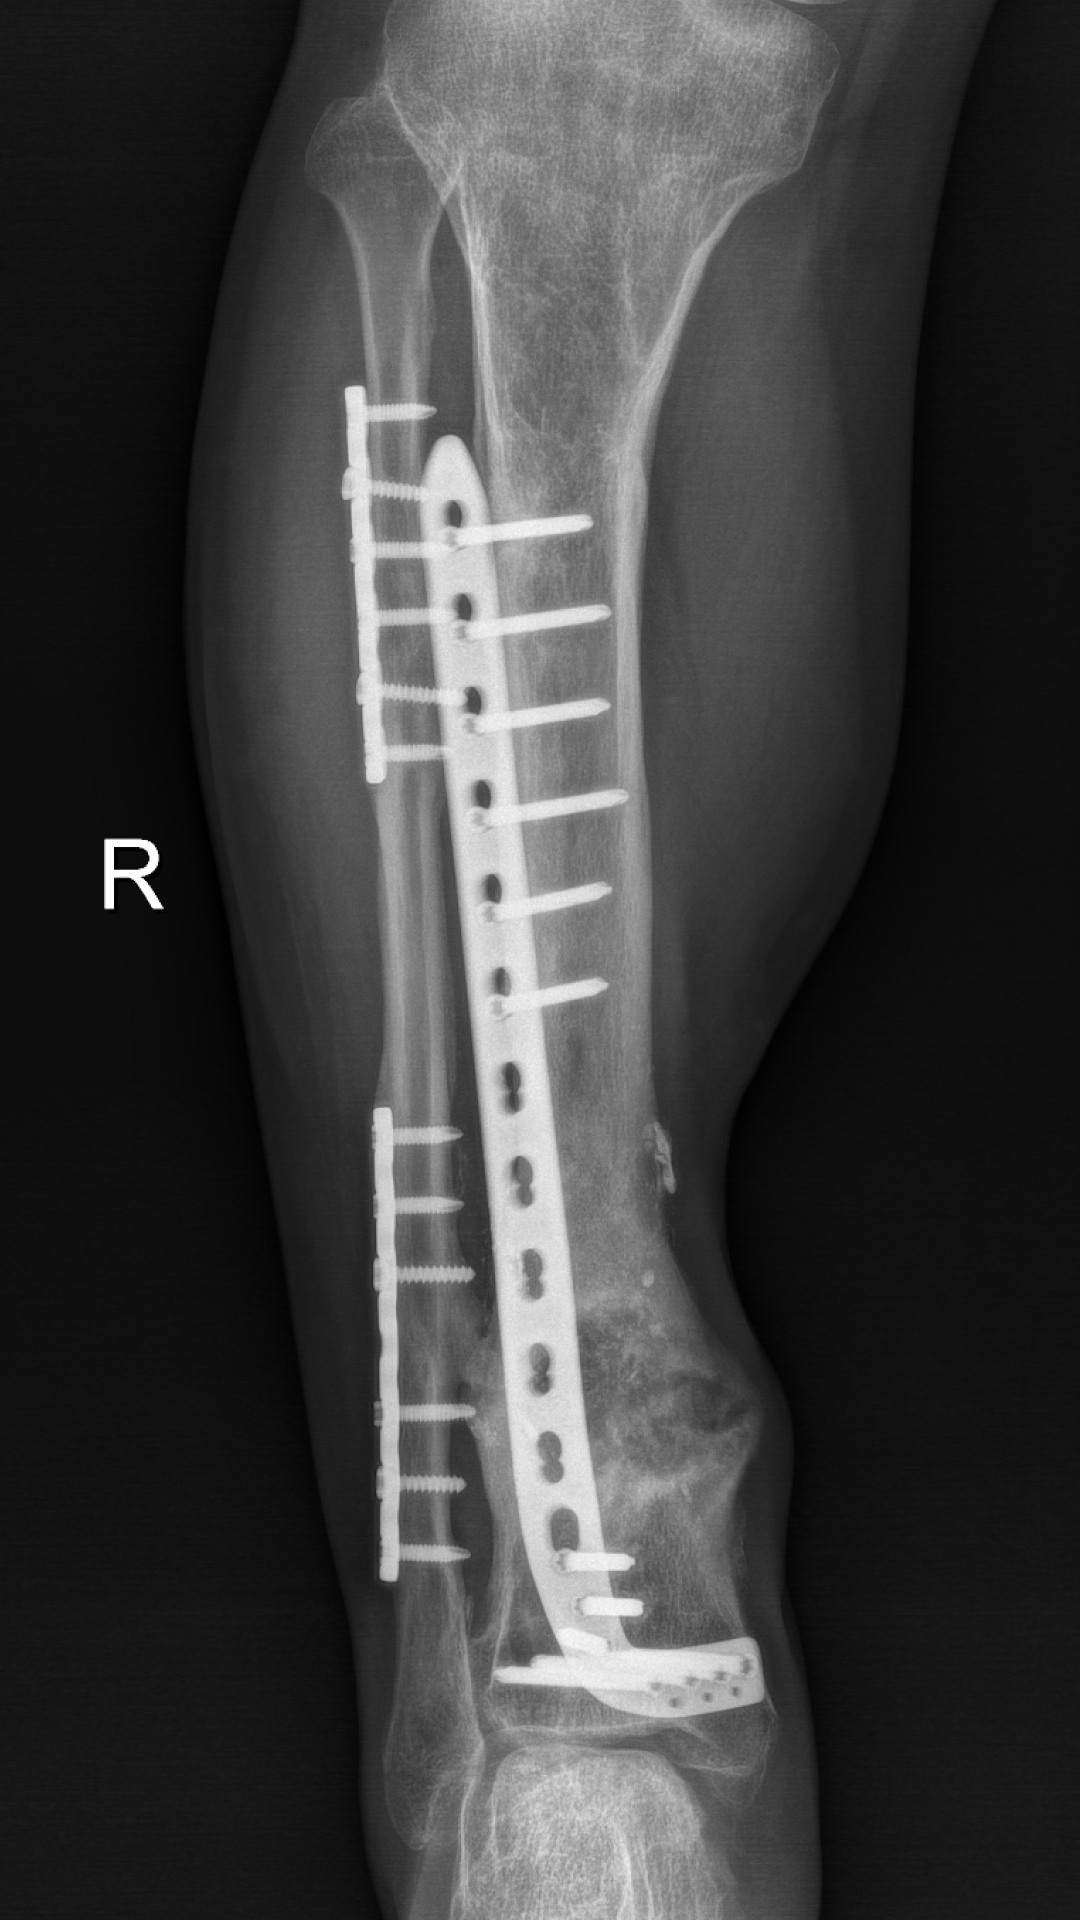

2、骨缺损重建

徐杨主任医师介绍,对于肢体毁损伤后期合并感染患者,保肢最大的难题是清创及骨与软组织重建,masquelet技术能够形成骨水泥诱导膜,不但能起到屏障作用,还含大量微血管,丰富血供,并能分泌各种促骨生长因子,具有成骨快、愈合率高的优点。尤其适合治疗长节段、严重感染性骨缺损病例。